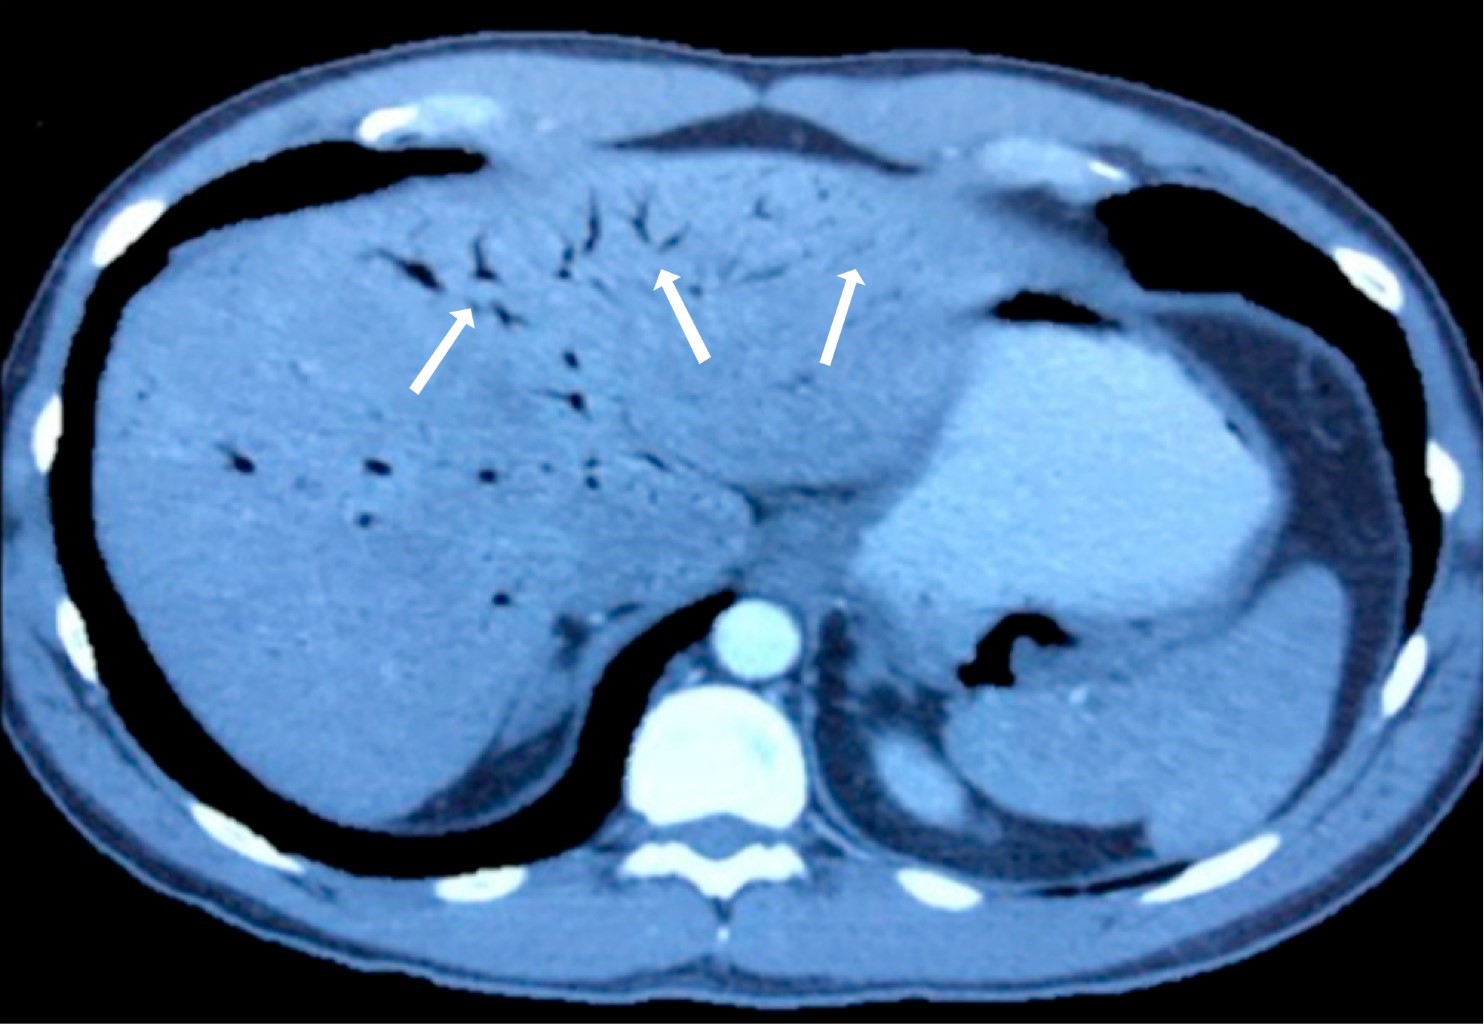

Pneumobilia Or Portal Venous Gas Clinical Diagnostic And Therapeutic